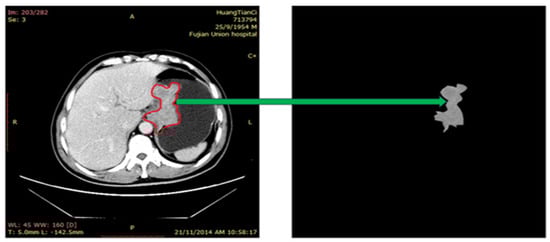

2.2. Image Preprocessing